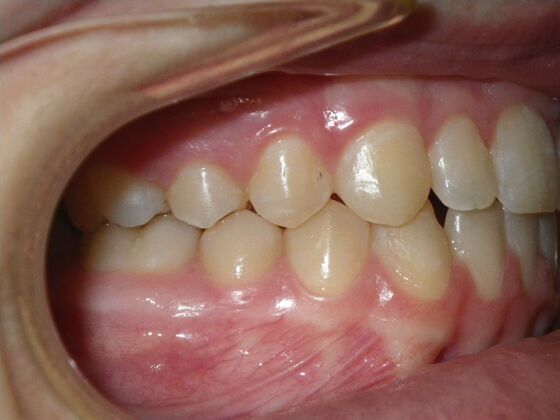

Orthodontics: Case 10

Description

This case presents with a dental midline discrepancy. The upper incisors are tipped toward the palate, which prevents the lower incisors from establishing proper arch form. The upper right molar has drifted forward, causing the upper midline to be skewed to her left. By distalizing the upper left molar, we can correct the midline discrepancy. Lastly, both upper and lower arches need expansion. All of this was completed with conventional straight wire appliances within 2 years.